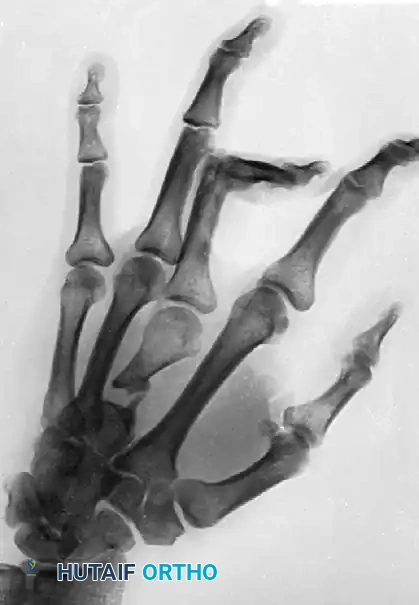

FIGURE 67-72: Malunited fracture of the fifth metacarpal neck treated by open reduction and fixation with one Kirschner wire inserted obliquely. This is rarely necessary because the normal motion of the fifth carpometacarpal joint permits tolerance of up to 40 degrees of angulation at the fracture site.